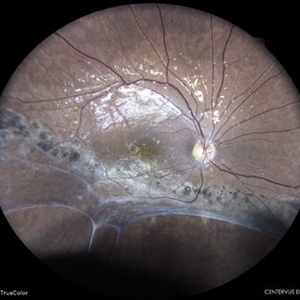

Status Post Scleral Buckling

Jan 26 2022 by Akansha Sharma

Wide field fundus photograph of a 55-year-old male with a scleral buckle in situ post scleral buckling performed 15 years back.

Photographer: Dr. Akansha Sharma - Retina Foundation, Ahmedabad

Condition/keywords: color wide field, encircling scleral buckle